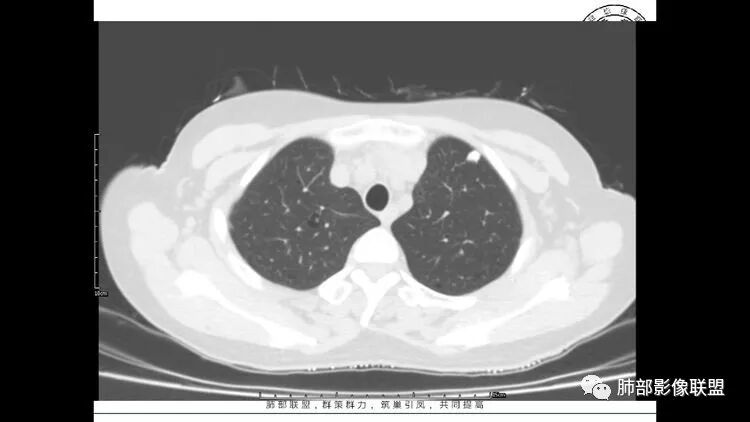

胸CT:1.双肺多发囊性变,以中下肺为主,病变边缘可见肺动脉,部分囊内可见分隔及肺动脉,双下部分肺野周围可见小叶中心结节及树丫征。

2 左肺上叶尖后段 右肺上叶前段 右肺下叶外基底段 结节影,边界清楚,可见柔软毛刺,左肺下叶后基底段混合密度影。

双肺多发磨玻璃结节,其内可见空腔,周围边界清晰,多发囊,左肺实性结节。考虑间质性肺炎,LIP可能性大。鉴别腺癌。

患者中年女性,因右眼红痛1天就诊。胸CT:双肺多发囊性变及结节影,囊以中下肺为多,部分囊内可见分隔及肺动脉,结节部分为实性,部分为混合性,边缘光滑,未见明显毛刺、棘突、胸膜牵拉及血管集束征象。双中下可见支气管扩张及树丫征。淋巴结无明显肿大。综合考虑:一元淋巴细胞间质性肺炎。多元鉴别肺腺癌并转移等恶性病变。

中年女性,双肺多发囊性变,以中下肺为主,病变边缘可见肺动脉,部分囊内可见分隔及肺动脉,左肺上叶较大结节,可见分叶、月牙铲,左肺下叶、右肺中叶磨玻璃病灶,边界清楚,内有空泡,结节,可见尖后段 右肺上叶前段 右肺下叶外基底段 结节影,边界清楚,纵隔淋巴结肿大,

中年女性,因“角膜炎”入院,自用眼液2年,(眼干?)肺部:双肺多发类圆形薄壁气囊+实性结节+GGO,下肺分布为主,纵隔淋巴结肿大,考虑淋巴系统增殖,LIP可能性大,可能继发于干燥综合症;左肺下叶的混合磨玻璃结节形迹可疑,边界清晰,内部疑似空泡,扩张扭曲支气管,极像肺癌,伴双肺转移?待排吧

1.左下肺腺癌;2.两肺弥漫性病变(多发囊腔、部分囊壁不规则,分布无特异,结节,空洞,树芽征,GGO),结合眼部情况首先考虑LIP,不典型感染(病毒或其他)待排。

左肺下叶混杂密度病灶,其内可见空泡,周围ggo清楚,考虑浸润性腺癌。双肺散在多发薄壁囊腔和实性结节,以胸膜下及血管旁分布位于,气囊可见血管贴边征,双肺小叶间隔及中央间质增厚,局部可见磨玻璃影及树芽征,纵隔内淋巴结肿大,考虑LIP

综上,考虑左下肺浸润性腺癌+LIP

LIP影像重要线索一句话:

双肺下叶分布为主的间质改变(磨玻璃影、小叶间隔增厚)、散在气囊影(常有血管贴边)、边界不清小结节